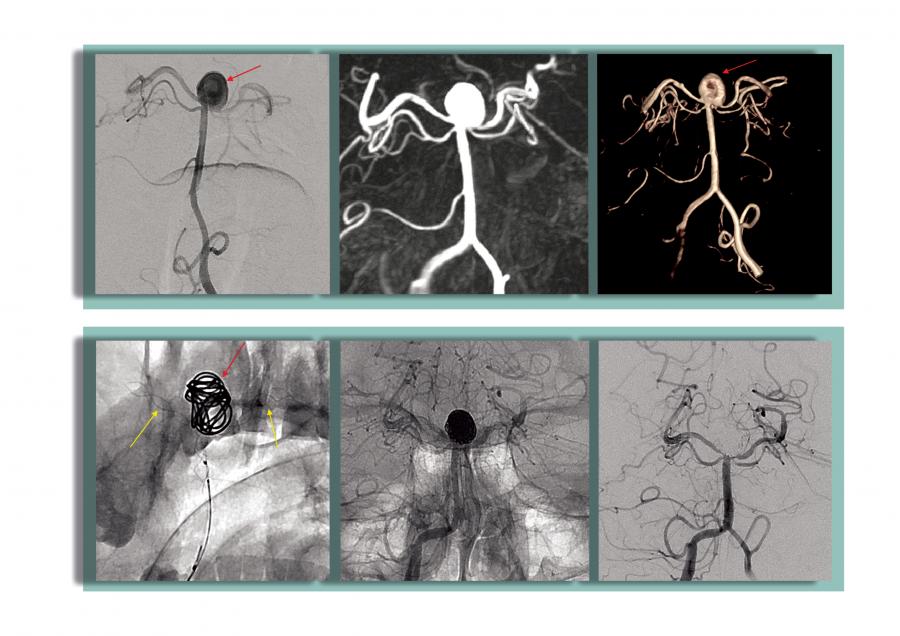

48 yaşındaki diğer hastanın yapılan ilk incelemelerinde, hastada beyin kanaması bulgularına rastlandı. Beyin Damarları Anjiyografisi’nde, hastanın beyninde 8 mm çapında baloncuk (anevrizma) tespit edildi. Patlaması an meselesi olan anevrizmaya, kapalı yöntemle kasık atar damarından girilerek sağ ve sol arka beyin damarını korumak için stent yerleştirildi ve kritik olan anevrizma, koil (tel yumak) ile kapatıldı. Zorlu geçen bu girişimsel işlem, hastanın büyük ve riskli bir ameliyata gerek kalmadan şikâyetlerini ortadan kaldırıp kısa bir sürede şifa bularak taburcu olmasını sağladı.